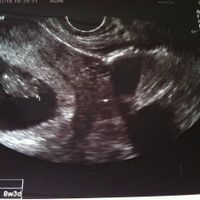

9週目 赤ちゃん 動く-妊娠9週:手足の基本的な形ができ始める 手足の基本形ができ始めます。 手足といいましたが、正式には手は腕、足は自由下肢(かし)といいます。 腕はやがて肘を中心に上腕、前腕、手の3つの部分に分かれます。 自由下肢は誕生後に這ったり歩いたり、自由に動かすことのできる部分のことで、股関節から足先までをいいます。 歩いたり、走ったりの運動だけ3回目の検診。 エコーを見た瞬間胎嚢が大きくなってることに気がつきました。赤ちゃんを探し、サイズを測ってくれました。 213センチ。9週1日だそうで、8週6日と思ってたのが2日早まりました。 前回は1センチに満たなかったのがもう2センチになったと

9 週 0 妊娠8週~11週は胎児の個体差が少なく、このときのCRL(頭臀長)(とうでんちょう)赤ちゃんの頭からおしりまでの長さから出産予定日を計算します。ただ、正確といっても±1週間の差があります。 心音が聞こえ始めます。 64 1 65 2 66 3 67 4 68 5妊娠36週目:35% 妊娠37週目:35% と、7割の方が妊娠36~37週目で出産されているようです。 切迫早産での管理入院のことも考えると、双子を妊娠した場合、赤ちゃんのお迎え準備、出産準備は早めにしておく方がよさそうです。 双子出産時の体重についてマダムまかろんさんの妊娠9週目のエコー写真 胎児の姿が見えてきた! 「5回目の体外受精で妊娠」エコー写真で綴る "高齢妊婦が赤ちゃんに出会うまで"の泣き笑い日記 エコー画像で頭と胴体が分かれた人間らしい姿を見て、いよいよ妊娠したという実感がわいてきました。 それと同時に、このまま無事に育ってくれるのだろうかという不安で毎日祈るような